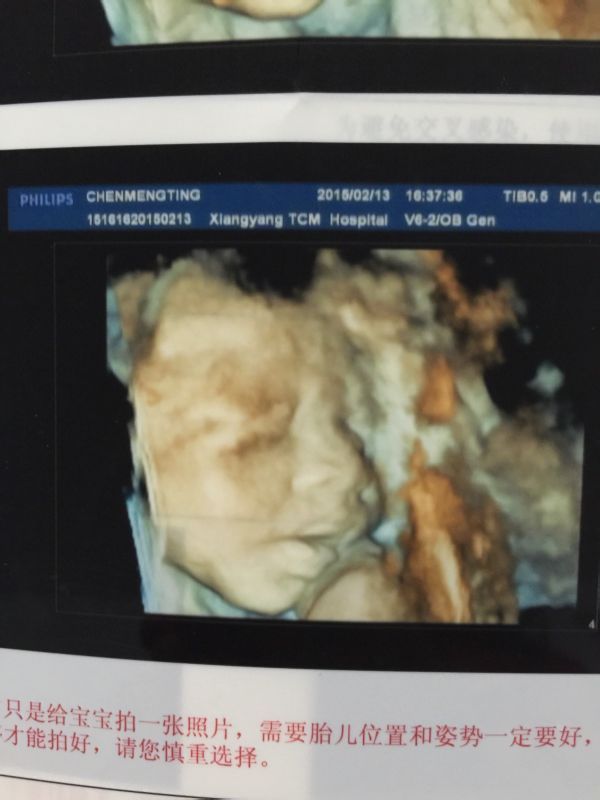

麻烦医生帮我看看我这是孕25周做的三围彩超,说胎儿左心室内可见一强回声光斑,是怎么回事啊?下面有单 子请医生帮我看看,谢谢啦!而且给宝宝拍的照片也好不清楚,不知道旁边是些什么东西! 点击展开 匿名用户 2015-02-13 18:19 为您推荐: 其他回答 你好,大部分心内强回声随着孕周的增加,逐渐消失,一小部分可能到出生后在彩超检中还能看见,心内强回声还可能与染色有关,建议结合唐筛结果,定期复查。 cn#BkkGGQBppp 2015-02-13 18:22 相关问题 宝宝三围彩超、左心室腔内可见一稍强回声光点是怎么回事呢、严重吗? 宝宝三围彩超、左心室腔内可见一稍强回声光点是怎么回事呢、严重吗? 彩超显示胎儿左心室见1 5X1 5MM强回声光斑,这是不是说胎儿心脏有问题???